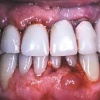

Krooniline parodontiit on mikroobide poolt põhjustatud hammaste tugikudede põletik, mille tulemusena tekib progresseeruv alveolaarluu (nähtav röntgenograamil) ja periodontaalligamendi destruktsioon, igemetaskute moodustumine, igeme retsessioon või mõlemad kahjustused kombineeritult. Krooniline parodontiit on...